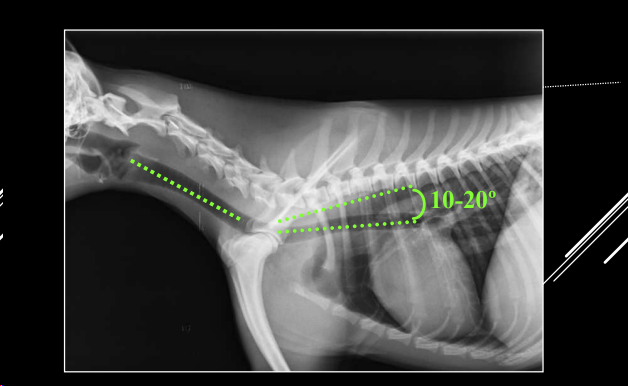

- Proyección LL.

- Cabeza y cuello rectos (evitar hiperextensión).

- Divergencia 10–20° con raquis torácico.